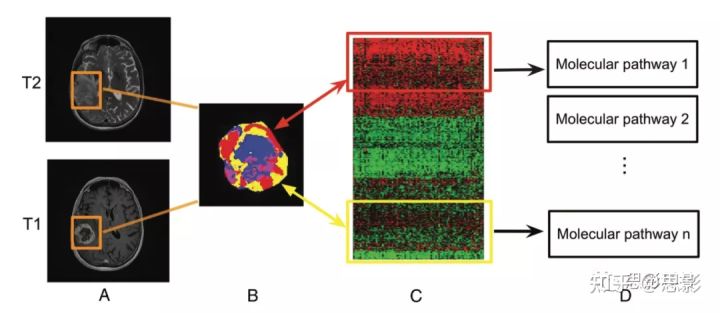

为了更好地定义基因组关系的成像,发展能够进行空间表征的子区域成像分析具有生物学价值(图2),因为它提供了一种手段来表征空间上不同肿瘤片段中的分子变化。

图2,胶质母细胞瘤分区成像与分子图谱的联系。在这个例子中,

肿瘤亚区(B)是通过联合聚类对比增强的T1WI和T2WI(A)来定义的。

这些子区域对应于红色(高T1WI和高T2WI)、黄色(高T1WI和低T2WI)、蓝色(低T1WI和高T2WI)和粉色(低T1WI和低T2WI)区域。定义的肿瘤亚区可以实现定量的空间表征,提供了一种无创评估特定分子活性的方法(C)和丰富的分子通路(D)。